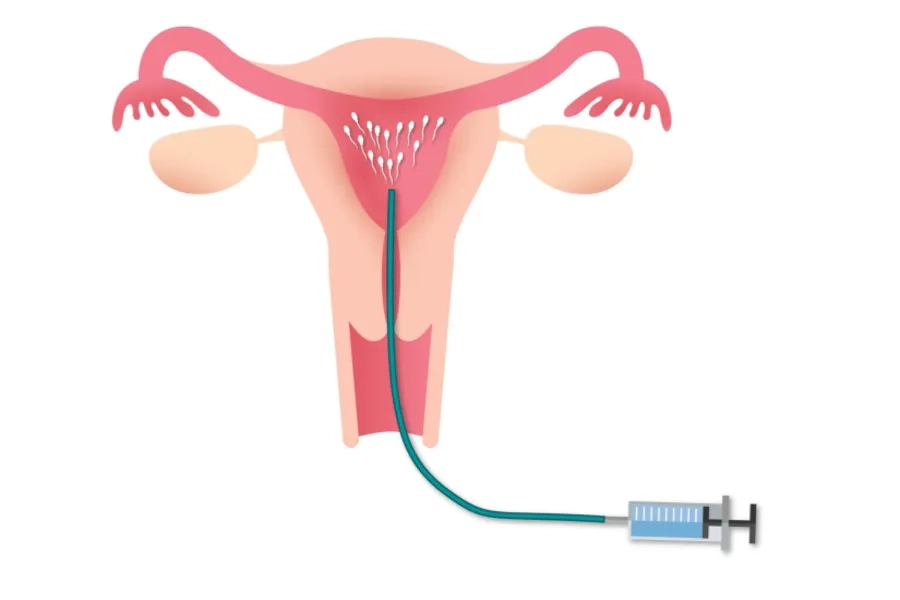

IUI (Intrauterine Insemination) - thụ tinh nhân tạo là kỹ thuật đưa trực tiếp tinh trùng đã được lọc rửa vào buồng tử cung của người phụ nữ. IUI giúp tinh trùng dễ dàng tiếp cận và thụ tinh với trứng, từ đó tăng cơ hội thụ thai. Phương pháp này thường áp dụng cho các cặp vợ chồng khó thụ thai do rối loạn phóng noãn, bất thường tinh trùng mức độ nhẹ hoặc vô sinh chưa rõ nguyên nhân.

IUI là phương pháp thụ tinh nhân tạo, bơm tinh trùng vào buồng tử cung

4. Bước 4: Thực hiện bơm tinh trùng

Bạn nên nằm ở tư thế giống khám phụ khoa. Tinh trùng đã lọc rửa được đưa vào tử cung bằng ống bơm chuyên dụng. Thủ thuật diễn ra nhanh chóng, chỉ mất khoảng 5 phút và hầu như không gây đau. Sau thủ thuật, bạn nên nghỉ ngơi khoảng 10-15 phút. Một số trường hợp có thể xuất hiện một lượng dịch âm đạo nhẹ do chất nhầy cổ tử cung hoặc dung dịch hỗ trợ bơm.

Kỹ thuật bơm tinh trùng vào buồng tử cung được thực hiện bởi đội ngũ bác sĩ chuyên khoa giàu kinh nghiệm